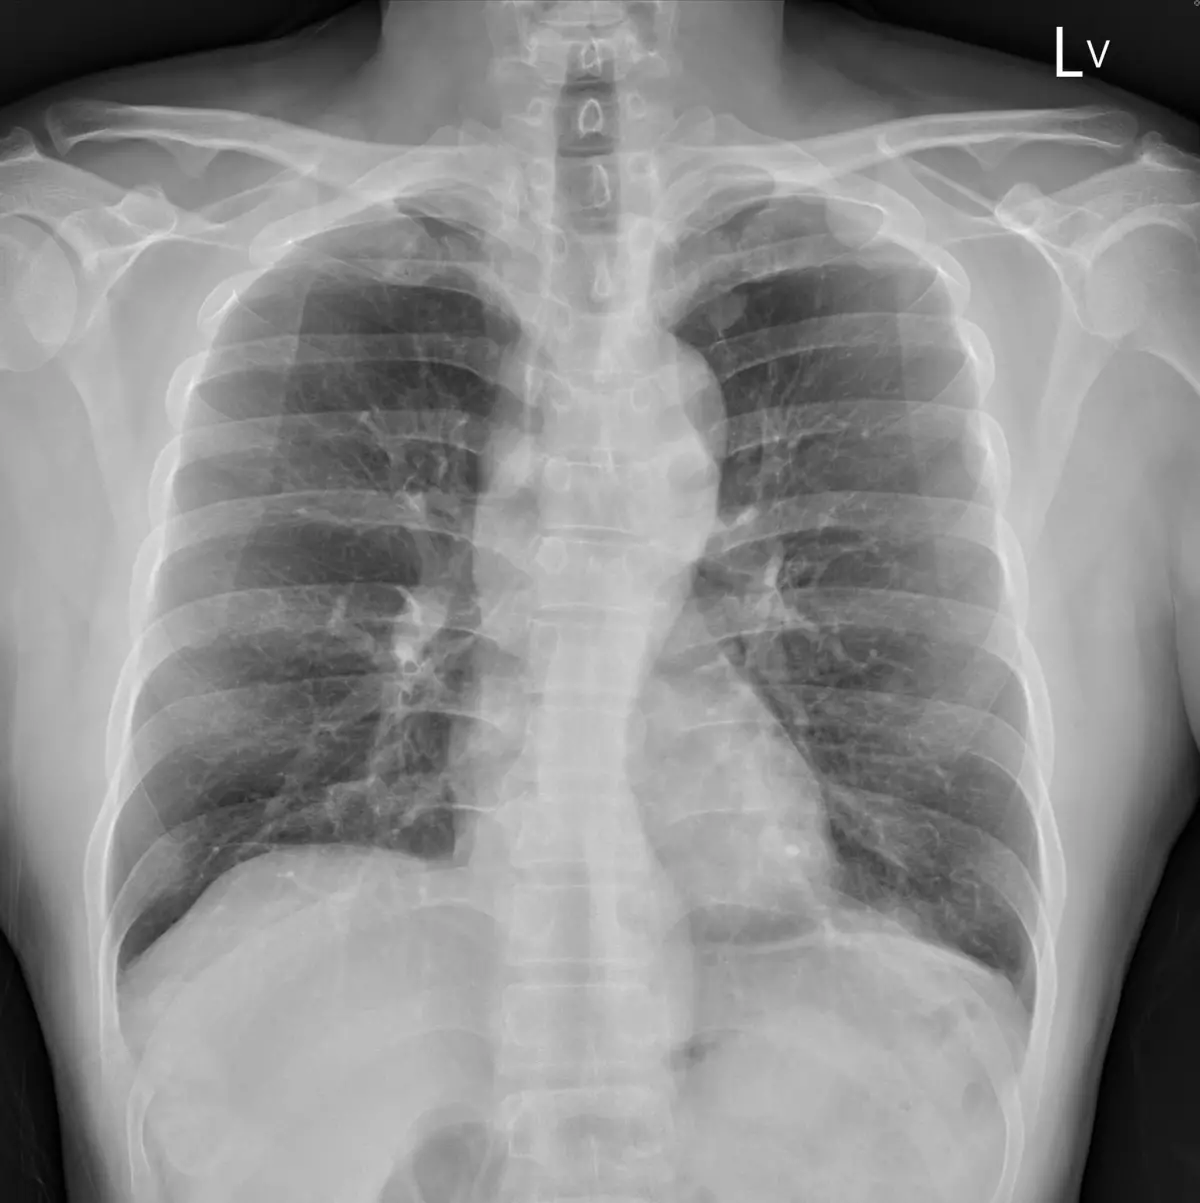

胸腔科醫師蘇一峰發文指出,一名四十多歲男性,平時不抽菸不喝酒,也沒有任何不舒服

,只是例行性身體檢查,卻發現胸腔有5公分腫瘤「癌症末期已經到處轉移」讓他忍不住

在診間哽咽快落淚。

蘇一峰還提到,這名病患每天都認真工作,去年的健檢還是正常,今年說X光有一點問題

,就來胸腔科檢查,沒想到照出5公分腫瘤加上轉移,變成末期癌症到處轉移。

蘇一峰先在文中放上X光圖,讓網友看看腫瘤,並在留言處附上圈起的腫瘤示意圖「躲在

主動脈裡面,五公分縱膈腔腫瘤」,讓網友也紛紛回應「好可怕,跟空污有絕對關係」、

「好可怕的無症狀」、「癌症讓人難受的是人生突然被畫下句點」。